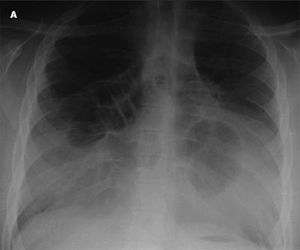

A 16-year-old boy with Down syndrome was referred for evaluation of nonspecific symptoms, including difficulty in breathing on standing up from a sitting position, dizziness, frequent abdominal pain, and diarrhea after ingesting fatty foods and milk. He had intermittent asthma exacerbations for which he occasionally used a β-agonist. He had no history of trauma, surgery, or allergies.